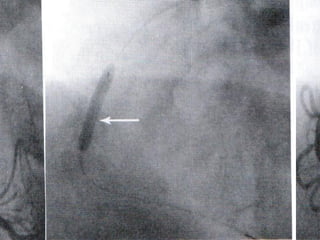

Unmasking of the restricting effect of ventricular

systole on mean coronary blood flow by induction of

ventricular fibrillation during constant pressure

perfusion of the LCA